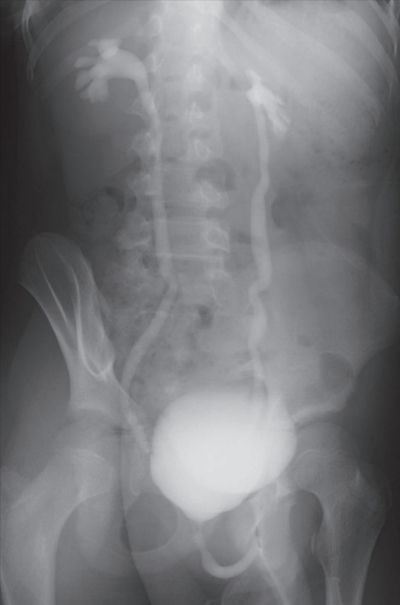

尿所見:蛋白 1 +、糖(-)、ケトン体(-)、潜血 1 +、沈渣に赤血球 1 ~ 4 /HPF、白血球 50~99/HPF を認める。尿路感染と診断し、入院のうえ、セフェム系抗菌薬の点滴治療を行った。解熱後に行った排尿時膀胱尿道造影像を別に示す。

この患児について正しいのはどれか。2 つ選べ。

d. 腎盂腎炎の予防に抗菌薬を投与する。

e. 99mTc-DMSA 腎シンチグラフィを行う。